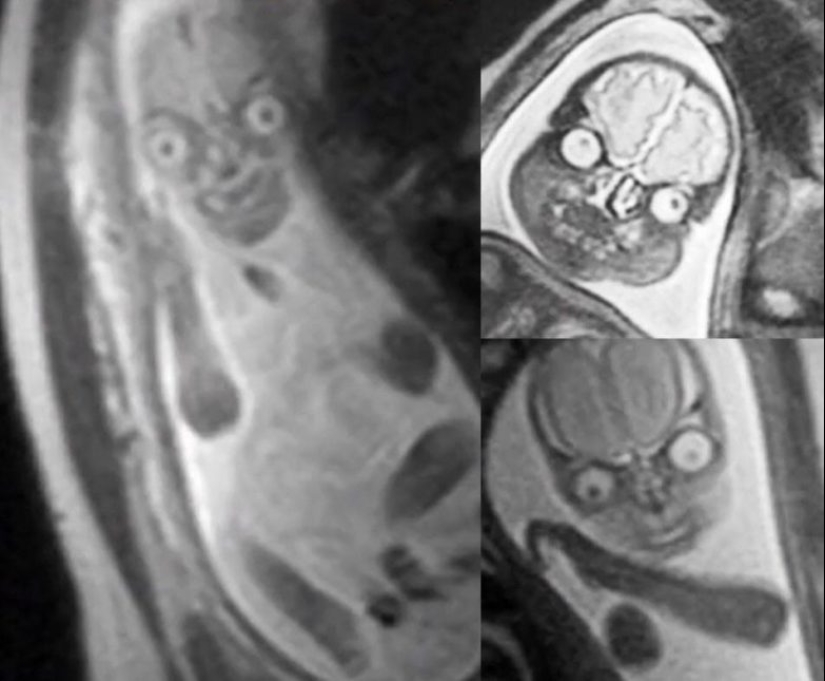

MRI of unborn children in the stomachs of pregnant women